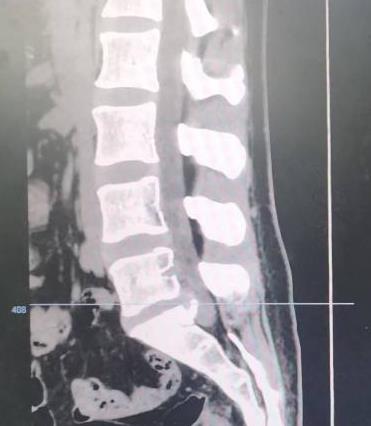

• 单侧双通道内镜下椎间盘切除术治疗钙化型腰椎间盘突出症的临床疗效分析

2025, 31(8):26-31. DOI: 10.12235/E20240693

摘要 (204) HTML (119) PDF 3.09 M (137) 评论 (0) 收藏

摘要:目的 观察单侧双通道内镜(UBE)下椎间盘切除术治疗钙化型腰椎间盘突出症(CLDH)的临床疗效。方法 回顾性分析2020年1月-2022年1月在该院行UBE下腰椎间盘切除术的25例单节段CLDH患者的临床资料。记录手术时间、术后住院时间和术后并发症情况。采用腰腿痛视觉模拟评分法(VAS)评分、腰椎日本骨科协会(JOA)评分和Oswestry功能障碍指数(ODI),评估术前、术后3 d、术后1个月和末次随访的临床疗效。末次随访时,采用改良Macnab标准,评估优良率。结果 术后随访12~24个月,平均(15.60±2.60)个月。手术时间为(58.67±10.73)min,术后住院时间为(4.65±0.63)d。术后3 d、术后1个月和末次随访时的VAS评分和ODI明显低于术前,JOA评分明显高于术前,差异均有统计学意义(P < 0.05)。末次随访时,根据改良的Macnab标准,15例为优,9例为良,1例为可,优良率为96.00%(24/25)。术后并发症:1例神经根腹侧硬膜囊撕裂,长度约5 mm,未行硬膜囊修补术,术后嘱患者卧床5 d,给予补液治疗,患者下床活动未诉头痛等不适,术后MRI显示:未见硬膜外大量积液;1例出现下肢感觉障碍,给予营养神经药物对症治疗,术后1个月随访时恢复。术后影像学检查显示:游离钙化组织基本被完全切除,神经根得到充分减压。末次随访时,未发现复发病例。结论 UBE下腰椎间盘切除术治疗CLDH安全、有效,值得应用于临床。